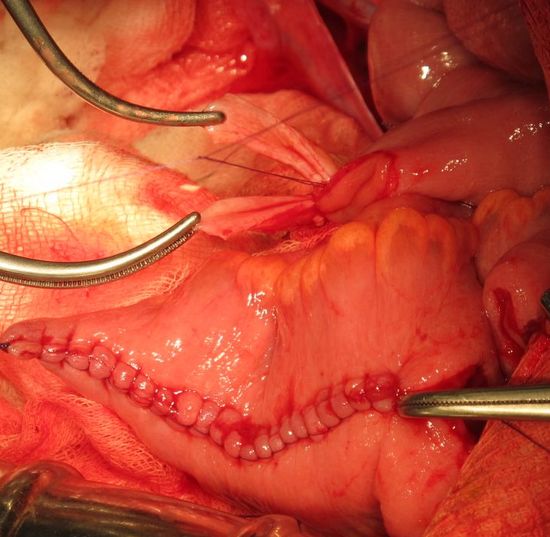

Формирование артифициального мочевого пузыря

ФОрмирования анастомозов между мочеточниками и недетубулиризированным участком необладера